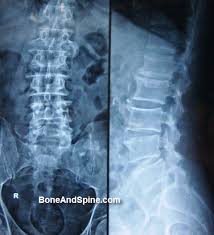

Serdülőkori gerincferdülés.

A gerincferdülés (scoliosis) a serdülő korra jellemző elváltozás.

A gerincnek vannak un. fiziológiás görbületei, a nyaki és deréktáji gerinc előre felé (lordosis), a háti és kersztcsonti szakasz hátrafelé görbül (kyphosis). A gerincnsk normál állapotban oldalirányú görbülete nincs, kivéve a szív magasságában lévő jelzett jobbra történő elhajlást ez azonban fiziológiás.

Serdülő korben, jellemzően 12-18 év között gyakori a gerinc nem fiziológiás görbületének kialakulása, melynek oka lehet alkatilag meghatározott, un. ízületi illetve kötőszöveti lazaság. A leggyakoribb ok azonban az, hogy a csont, szalgrendszer fejlődése nincs szinkronban az izomrendszer fejlődősővel, emiatt megbomlik a két rendszer közötti egyensúly, ami gerincferdülés kialakulásához vezethet. Elősegítő külső tényező az inaktív életmód, a mozgás hiánya, a súlyfelesleg.

Gyakori deformitás a háti görbület fokozódása a vállak előre esése ez az un. hanyag tartás.

A gerinc oldalirányó görböletei kialakulhatnak a háti és az ágyéki gerincszakaszon, ezt scoliosisnak nevezzük. Ilyen esetben nam csak az oldalirányú görbületről van szó, hanem ebben az esetben a csigolyák elfordulása un. rotaciója is fennáll.

Tünettena: a gerinc, a hát fájdalmasá válik, a mozgás beszűkül, a vállak és a medence valamelyik irányban dől, a bordaíveken kidudorodás, un. bardapúp alakul ki.

Az elváltozás diagnosztikája fizikális vizsgálatból és kétirányú röntgen felvétel elkészítéséből áll, ritkán szüksége CT vagy MR vizsgálat kiegészítésként.

A kezelés elsősorben konzervatív, gyógytorna, a törzsizmok (core izomzat) megerősítése, a rendszeres sport, testmoozgás, szükség esetén átmenetileg gyógyszeres támogatás.

Amennyiben a görbület bizonyos fokot (20fok) meghalad a fenti kezelések mellett méretre készített gerincfűző viselését rendeljük el, nagyobb görbület (40fok) esetén műtéti koorekció szükséges.

A folyamat a növekedés időszakában általában jól befolyásolható, ezt az időszakot funkcionális scoliosis idősakának nevezzük, később a növekedés befejeződése után az elváltozás már nem korrigálható, ilyenkor már csak a apanaszok csökkentése a cél. A felnőtt korban megmaradt gerincdeformitás gyors kopáshoz a csigolyák deformitásához, mészfelrakódásokhoz, mozgásbeszűküléshez estlen ideggyök érintettséghez vezet.